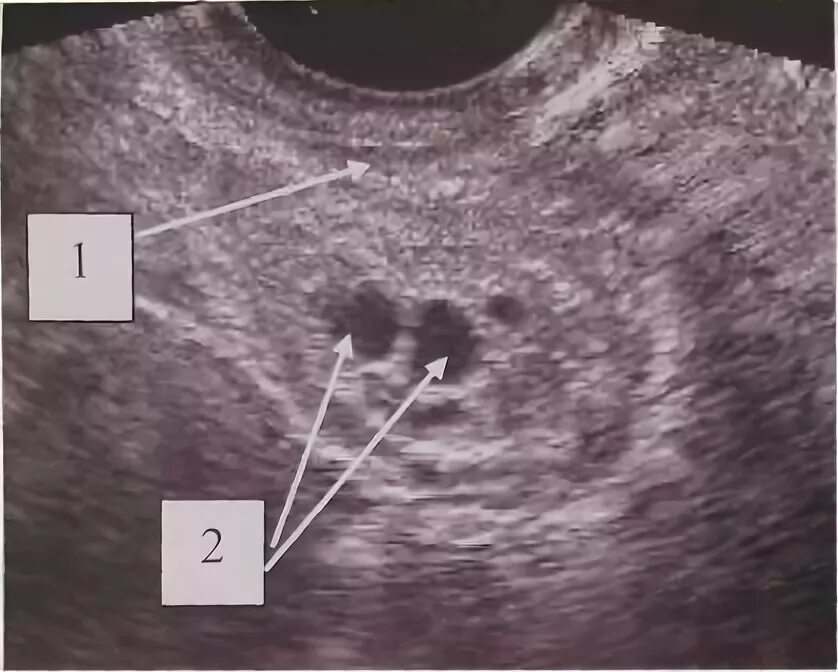

Как выглядят 2 матки